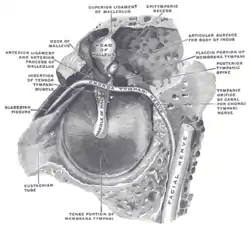

External and middle ear, right side, opened from the front (coronal section) Horizontal section through left ear; upper half of section

Horizontal section through left ear; upper half of section The right membrana tympani with the hammer and the chorda tympani, viewed from within, from behind, and from above